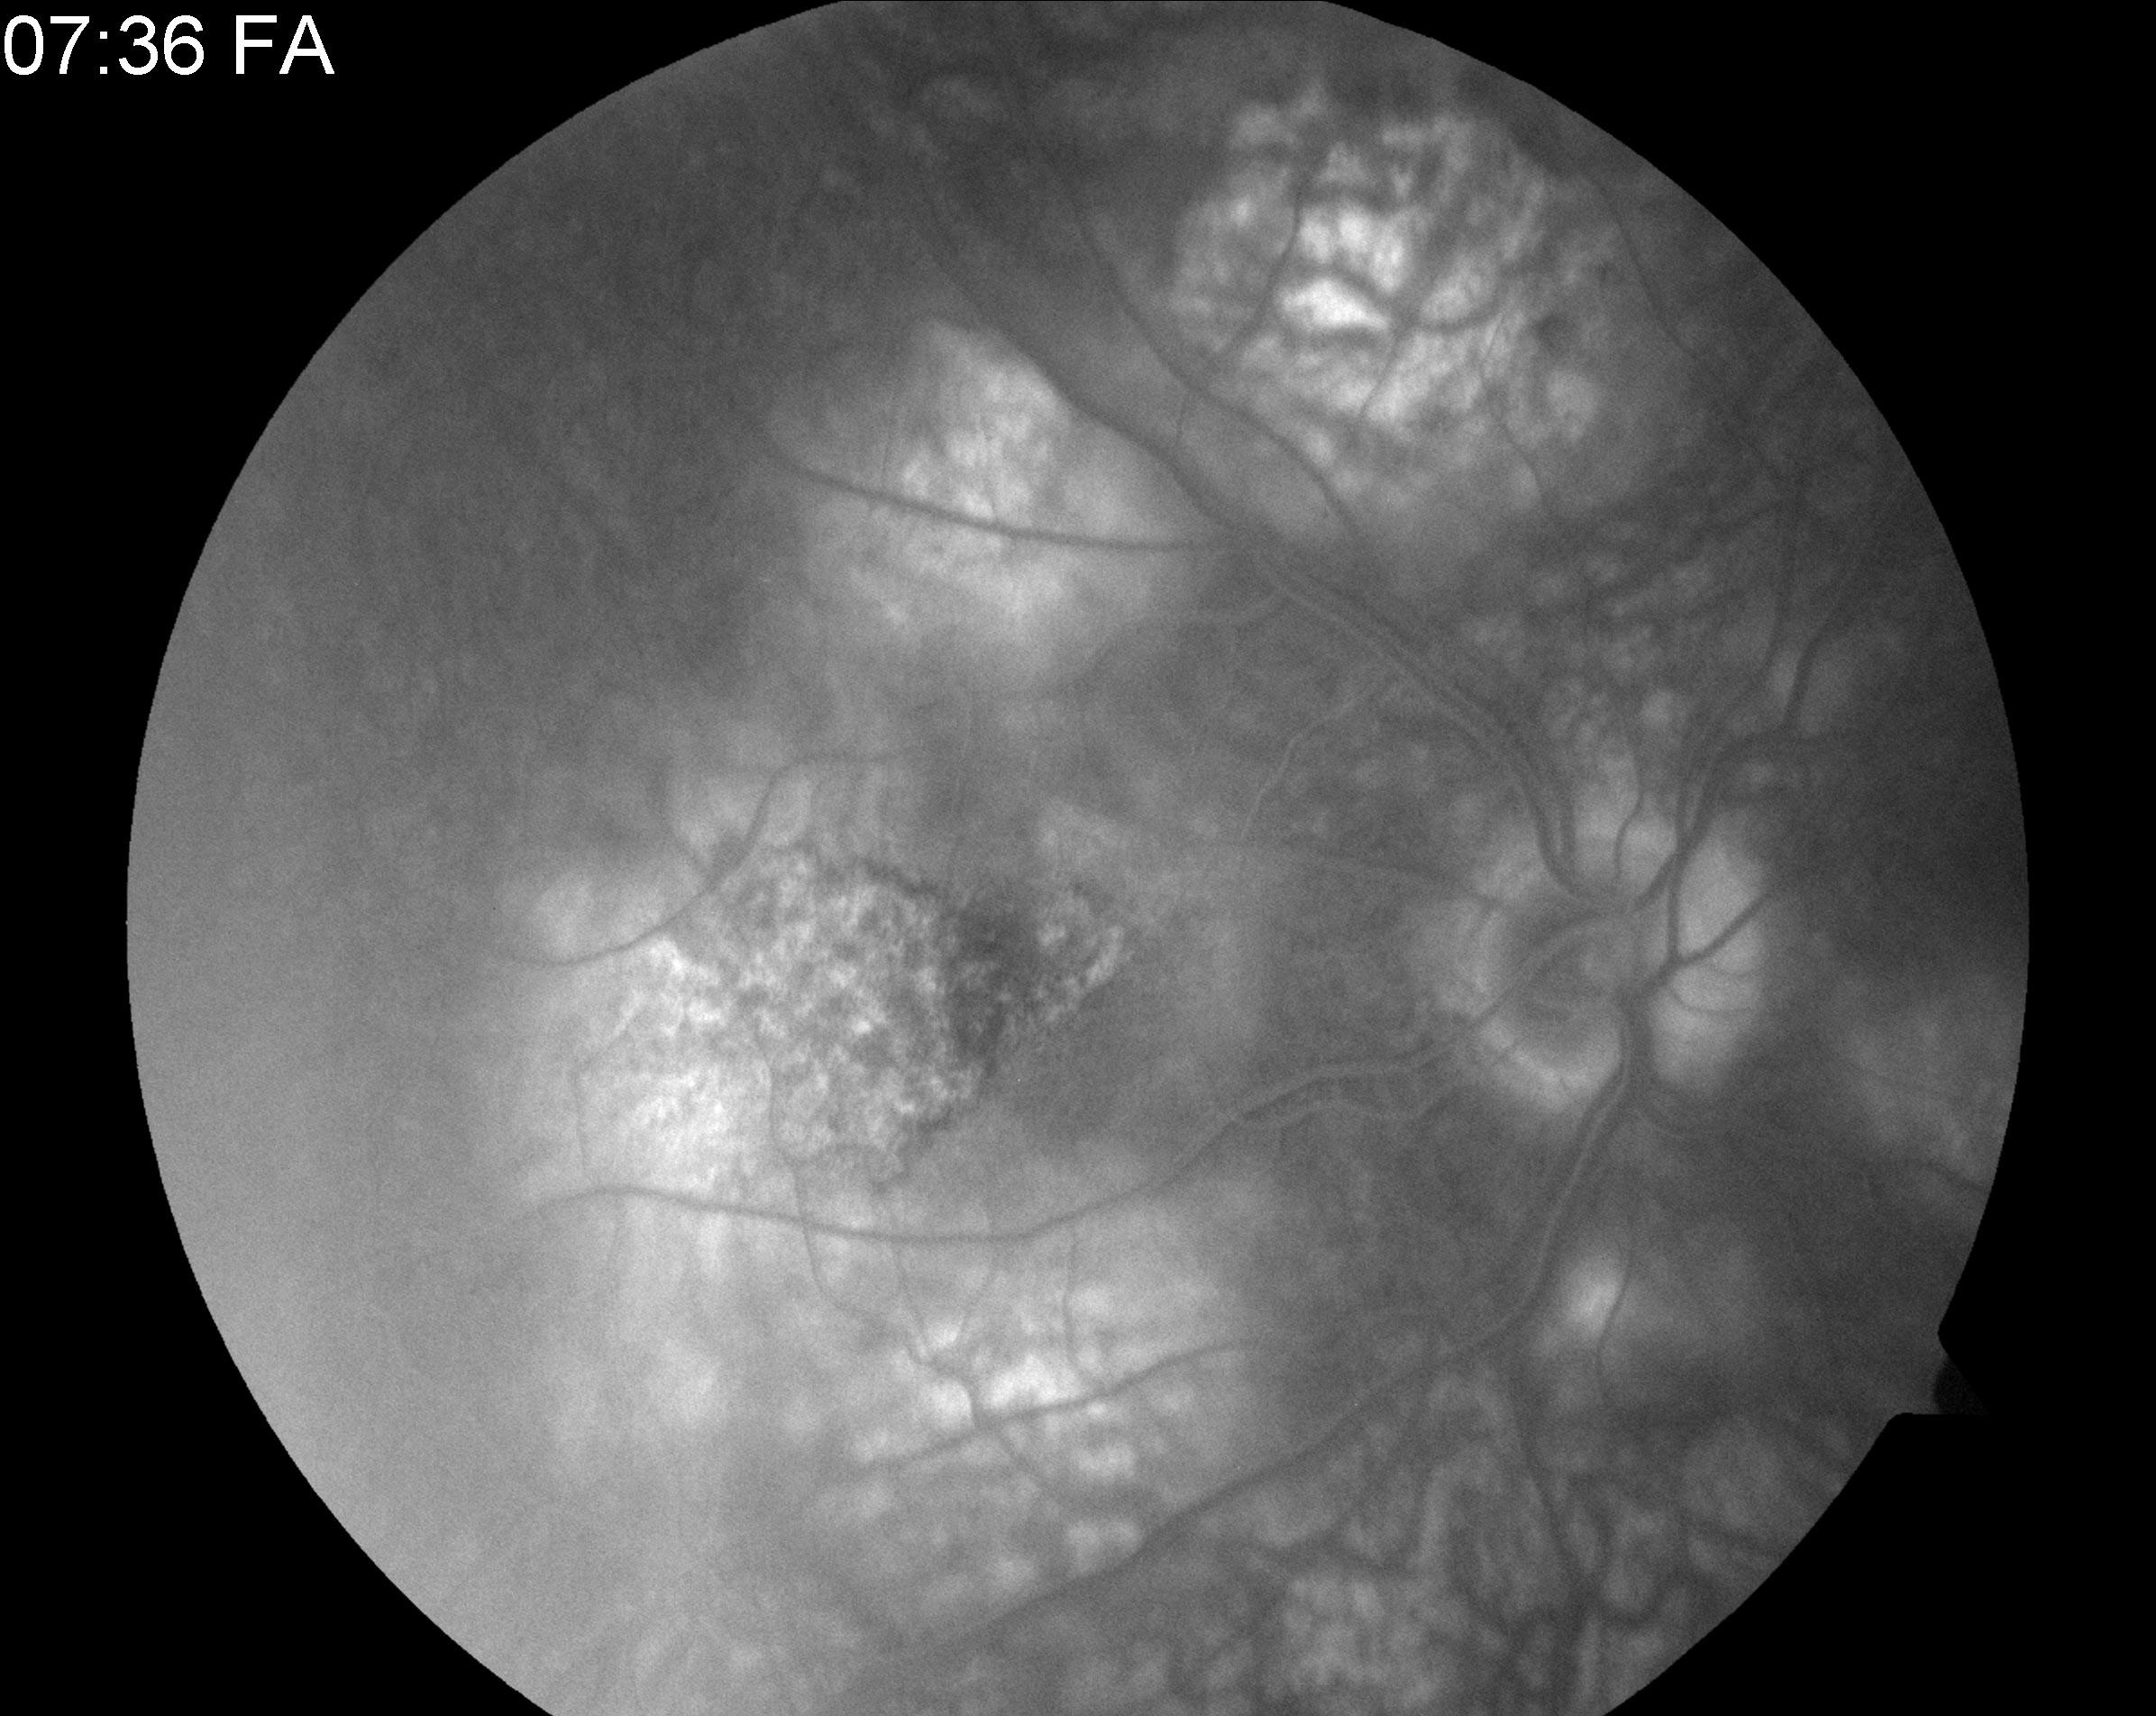

Fluorescein angiogram: late hyperfluorescence

| current | 10:47, October 2, 2010 | 2,392 × 1,904 (800 KB) | Elan002 (talk | contribs) | Fluorescein angiogram: late hyperfluorescence |